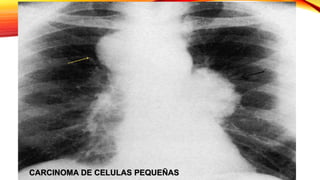

CARCINOMA DE CELULAS PEQUEÑAS

Representa el 20% de los TU pulmonares

malignos

Deriva de las células basales de tipo

neuroendocrino o células de Kulchitsky

Es de localización central y se asocia con

frecuencia a adenopatías mediastinicas

Es un TU de extrema malignidad con

gran facilidad para desarrollar metástasis

tanto por vía linfática como hematógena

Carcinoma de células pequeñas

• Localización prehiliar en el 80% y se asocia a

adenopatías mediastinicas.